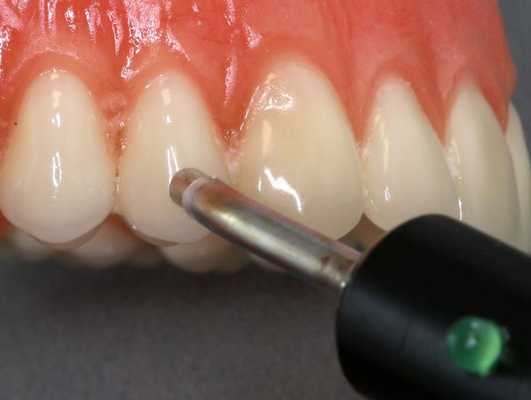

Диагностика периодонтита проводится на основании жалоб пациента, анамнеза заболевания, оценки общесоматического статуса, осмотра головы и шеи, полости рта, зуба, его перкуссии, зондирования и термопробы, электроодонтодиагностики (ЭОМ) и рентгенологического исследования. [10]

ЭОМ — это метод стоматологического исследования, основанный на определении порогового возбуждения болевых и тактильных рецепторов пульпы зуба при прохождении через неё электрического тока.

Холодовая проба, или термодиагностика, проводится двумя способами:

- на зуб дуют холодным воздухом при помощи пустера — стоматологического инструмента для подачи смеси воздуха и воды;

- в полость вносят тампон, смоченный в холодной воде.